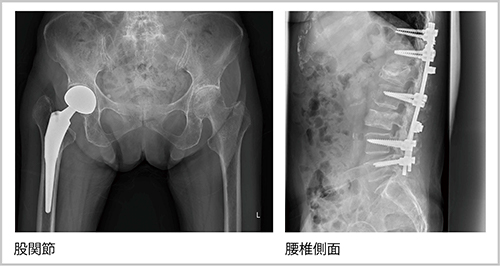

■CXDIによる臨床画像

さらに,FPD撮影の線量や画質について江原技師長は,「どの領域の撮影でも,CRと比べて半分以下の線量で十分に診断可能な画像を得られるようになりました。ポータブル撮影やブッキーを使用しない撮影では,散乱線低減処理を適用することで明瞭な画像を得られており,ポータブルの胸部撮影では線量を1/4程度にまで低減しています」と説明する。また,本郷技師は,「特に整形領域の画質が非常に良く,骨やインプラントのエッジが明瞭に描出されています」と述べる。